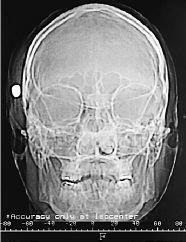

Fig. 1. Fig. 2.

Varón de 34 años que, tras una reyerta callejera, sufre herida por arma de fuego en zona craneofacial sin pérdida de conciencia. Al ingreso en la unidad de cuidados intensivos el paciente se encuentra somnoliento con apertura ocular a la llamada, lenguaje y movilidad normales. Presenta epistaxis bilateral, hematoma en anteojos y herida en ala nasal izquierda de unos 8 mm de diámetro, palpándose cuerpo extraño subcutáneo en zona retroauricular derecha. La radiografía simple de cráneo (fig. 1) demuestra la existencia de un proyectil en región temporal derecha. En la tomografía axial computarizada craneal (fig. 2) se identifica un trayecto intraparenquimatoso con sangre y aire en lóbulo temporal derecho orientado hacia una fractura de la calota craneal, quedando el proyectil alojado en los tejidos blandos inmediatos a la fractura. El hemisferio cerebral derecho muestra discreta expansividad. A pesar de la gravedad de las lesiones el paciente fue dado de alta 3 semanas después (escala de coma de Glasgow de 15), sin presentar ninguna complicación posterior.